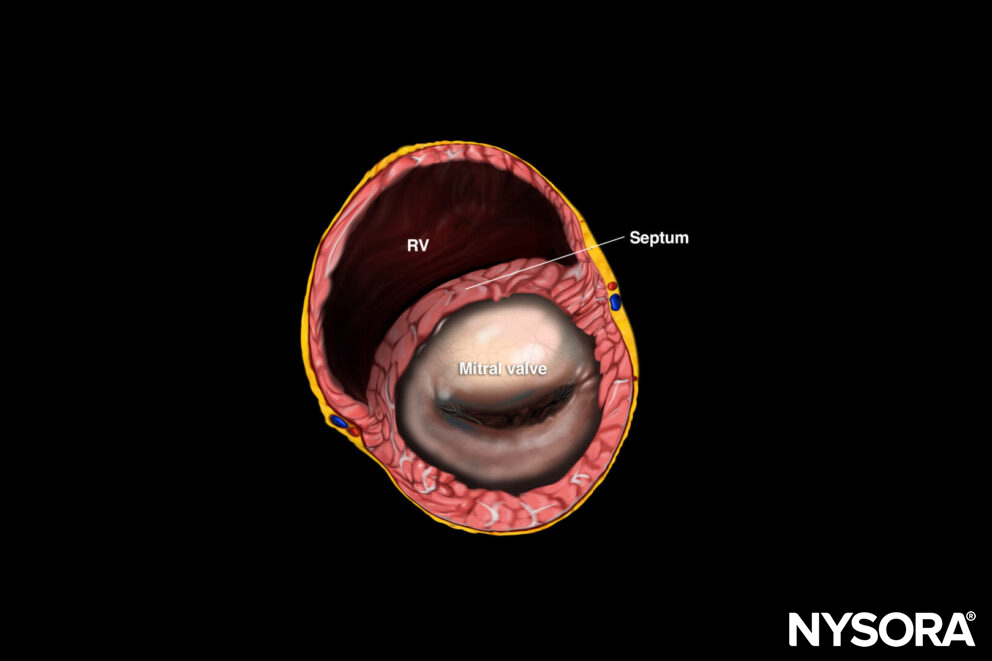

B. Mitral valve level: ‘Fish mouth’ view: Right ventricle and mitral valve.

The standard parasternal short-axis view cuts the heart through the transverse plane.

Sonoanatomy of the heart in the parasternal short-axis view. Right ventricle (RV), septum, left ventricle (LV), and papillary muscles.

Reverse ultrasound anatomy:

Reverse Ultrasound Anatomy of the heart in the parasternal short-axis view. Right ventricle (RV), septum, left ventricle (LV), and papillary muscles.